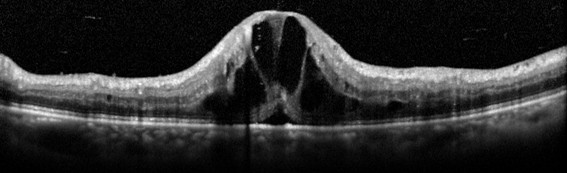

光干渉断層計(OCT)検査で、中心のむくみ(黄斑浮腫)の有無を確認します。